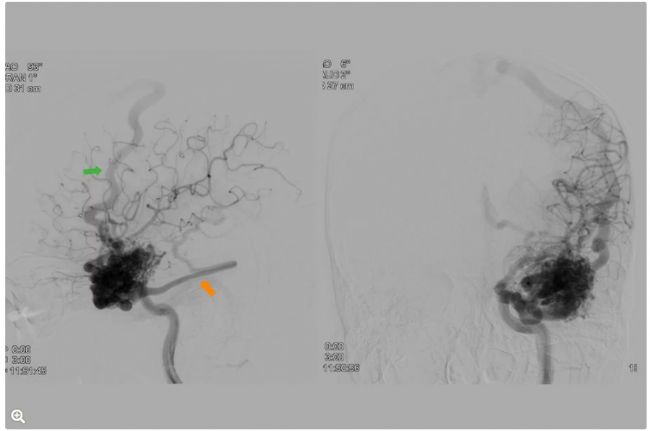

術前圖像:AVM引流

圖5:AP和側位投影。AVM通過上吻合靜脈淺表引流至上矢狀竇(綠色箭頭),并通過巖下竇進行深層引流(橙色箭頭)。